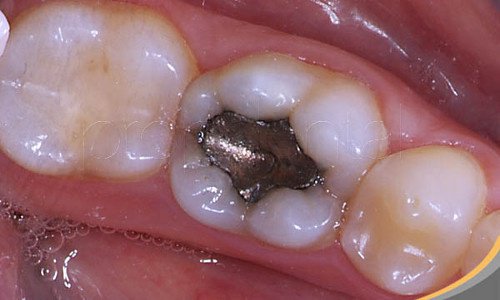

Амалгамата е материал със сребърен цвят, който представлява комбинация от няколко метала – най-вече меркурий. Използва се от зъболекарите за запълването на кухините, които се получават след развитието на кариес.

Пломбата от амалгама съдържа между 120 и 670 мг. меркурий, които постепенно се освобождават заради въздействието на слюнката, стомашните киселини, водата, високите температури и други фактори.